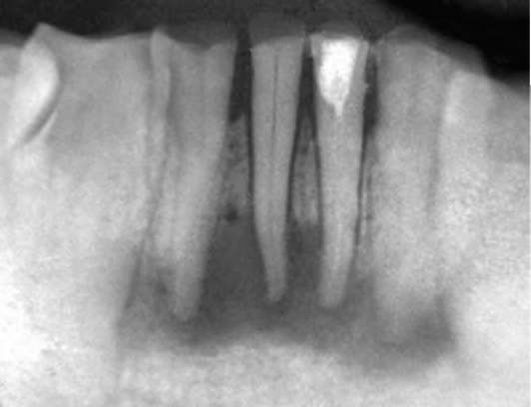

Рентгенологическую картину характеризует деструкция тканей у верхушки корня, где образуются различных размеров очаги разрежения костной ткани без четких границ (рис. 13-10).

image

Рис. 13-10. Внутриротовая рентгенограмма. Деструкциия костной ткани с нечеткими контурами у верхушек корней зубов 14, 15

Верхушка корня может быть резорбирована и укорочена. При отсутствии дренажа (свищевого или канального) апикальный периодонтит, сопровождающийся наличием грануляционной ткани у апекса, чаще других форм может обострять клиническое течение.

Диагностика основана на клинической картине и рентгенологических данных. На рентгенограмме при хроническом периодонтите обнаруживают типичные изменения - очаг разрежения костной ткани в области верхушки корня. Линия периодонта в этом отделе не видна из-за инфильтрирующего роста грануляционной ткани, приводящего к рассасыванию стенок лунки, а также цемента и дентина корня. Поверхности их становятся неровными. Эту неровность выявляют более отчётливо со стороны костной ткани, в которую из периодонта идут небольшие выросты. Компактную пластинку стенки альвеолы обнаруживают лишь в боковых отделах. У пациентов с периодонтитом и вовлечением в воспалительный процесс тканей пародонта происходит резорбция кости как по горизонтали, так и по вертикали.